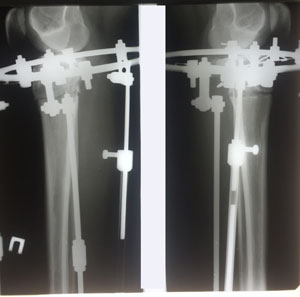

Рентген в 20 дней после операции.

Вложения